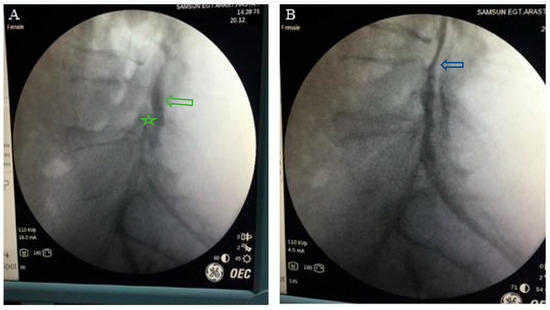

3.4. Complications

The most common complications included headache and incisional pain, each affecting five (6.7%) patients. Other observed complications included dural tear in four (5.3%) patients, motor loss in two (2.7%) patients (one of which was temporary), and infection in one (1.3%) patient. Some individuals experienced multiple complications, with a total of 10 (13.3%) patients developing complications. Among these 10 patients, 8 had a history of lumbar surgery, and 6 had granulation tissue present. One patient who developed motor loss (foot drop) underwent surgical intervention (Figure 4).

We encountered several complications related to epiduroscopy, including transient headaches (n = 5), pain at the site of scope insertion (n = 5), dural tears (n = 4), motor loss (n = 2), and mild meningitis (n = 1). Except for one patient, all symptoms resolved following bed rest and conservative treatment with medications. A single instance of foot drop due to a laser complication required emergency surgery and was successfully managed. The same patient also developed signs of mild meningitis postoperatively and was treated with intravenous antibiotics during hospitalization. It could not be determined whether the meningitis occurred following the epiduroscopy or the subsequent laminectomy. The patient made a full recovery after completing antibiotic therapy.

Various complications, such as postoperative headache, pain at the incision site, motor loss, and infection, have been reported with SELD [11], and the “60-limit rule” is optionally recommended for these complications [41]. We performed our procedures in accordance with this recommendation. The most common complications included headache and incisional pain, each affecting five patients. Among the major complications, dural tears occurred in four (5.3%) of our patients. Dural tear rates associated with SELD were documented in the literature to range from 1.7% to 7% [7,37]. In patients with a history of previous surgery, the incidence of dural puncture is notably higher compared to those without a surgical history. This increased rate may be associated with anatomical changes and adhesions resulting from prior surgeries, which complicate catheter guidance [41]. In our patient population, 74.7% had a prior surgical history, which may explain the relatively high rate of dural puncture. Notably, in patients who undergo epiduroscopy with laser application, a significant complication arises from thermal damage to the nerve roots, leading to motor nerve dysfunction. Therefore, special attention is required during the laser procedure [9]. In our patient series, motor loss was observed in two patients following laser discectomy, and one of them required emergency surgery.

Figure 4. During the SELD procedure performed for a right paramedian disc herniation (blue arrow) at the L3-L4 level (a), the patient developed weakness in right knee extension following laser discectomy. Postoperative MRI findings (b) revealed cranial and foraminal migration of the paramedian disc (red arrow). The patient underwent a right L3-L4 laminectomy (green arrow) and discectomy one day after the procedure. Postoperative MRI findings following the surgery are shown in (c).